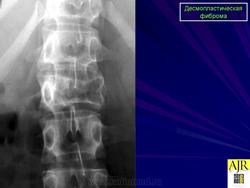

Десмопластическая фиброма редкая локально агрессивная внутрикостная опухоль, характеризующаяся продукцией опухолевыми клетками пучков коллагеновых волокон. Встречается в любом возрасте (чаще у лиц моложе 30 лет), с равной частотой у мужчин и женщин. Локализуется в основном в эпифизах и метафизах длинных костей (бедренная, плечевая, большеберцовые кости), плоских костях (кости таза, лопатка), нижней и верхней челюстях.

Рентгенологически остеолитический очаг, вызывающий вздутие истончённой кортикальной пластинки.

Десмопластическая фиброма